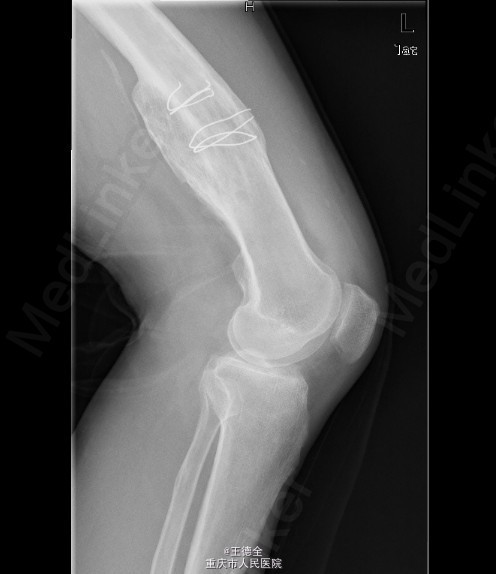

患者男,40岁,因“左股骨下段骨折术后4+年,左膝反复肿痛2年余”入院;自诉于4年前不慎被石块砸伤左大腿,伤后即觉左大腿疼痛,流血,左下肢活动障碍,患者伤后即到当地医院就诊,诊断为:"左股骨下段开放性骨折",予骨折切开复位内固定术,术后3个月下地行走,术后内固定螺钉松动、脱落,近两年来出现左膝关节肿胀、疼痛,活动时肿胀、疼痛症状加重,无畏寒发热、肢端麻木等,患者病后曾到当地医院就诊,予服药治疗后症状无明显好转,为进一步诊治遂来我院就诊,门诊拟"左膝骨性关节炎"收住我科,病程中,患者一般情况尚可,睡眠、饮食可,大小便正常,体重无明显改变。目前积极完善术前检查,拟做关节镜下关节清理术+左膝腘窝囊肿切除手术治疗。